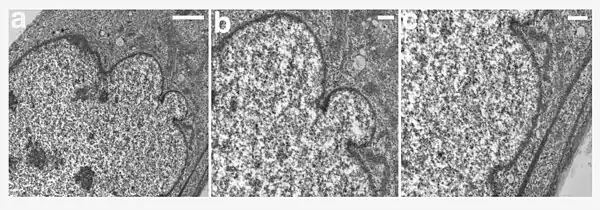

Ultrastructural analysis of the nuclear envelope in fibroblasts from a subject with HGPS. Low magnification transmission electron microscopic image of a passage 10 PT001 nucleus showed several herniations (a). Two higher-magnification images of the same nucleus at sites of blebs (b and c) showed a close apposition of the chromatin to the nuclear envelope. In a, b, and c, the nucleus is to the left. Scale bars correspond to 2 μm in panel a, and 500 nm in panels b and c.

Hutchinson-Gilford syndrome (HPGS) is a autosomal dominant genetic disorder.[8] HPGS is caused by mutations that weaken the structure of the cell nucleus, making normal cell division difficult. The histone mark H4K20me3 is involved and caused by de novo mutations that occurs in a gene that encodes lamin A. Lamin A is made but isn't processed properly. This poor processing creates an abnormal nuclear morphology and disorganized heterochromatin. Patients also don't have appropriate DNA repair, and they also have increased genomic instability.[9]